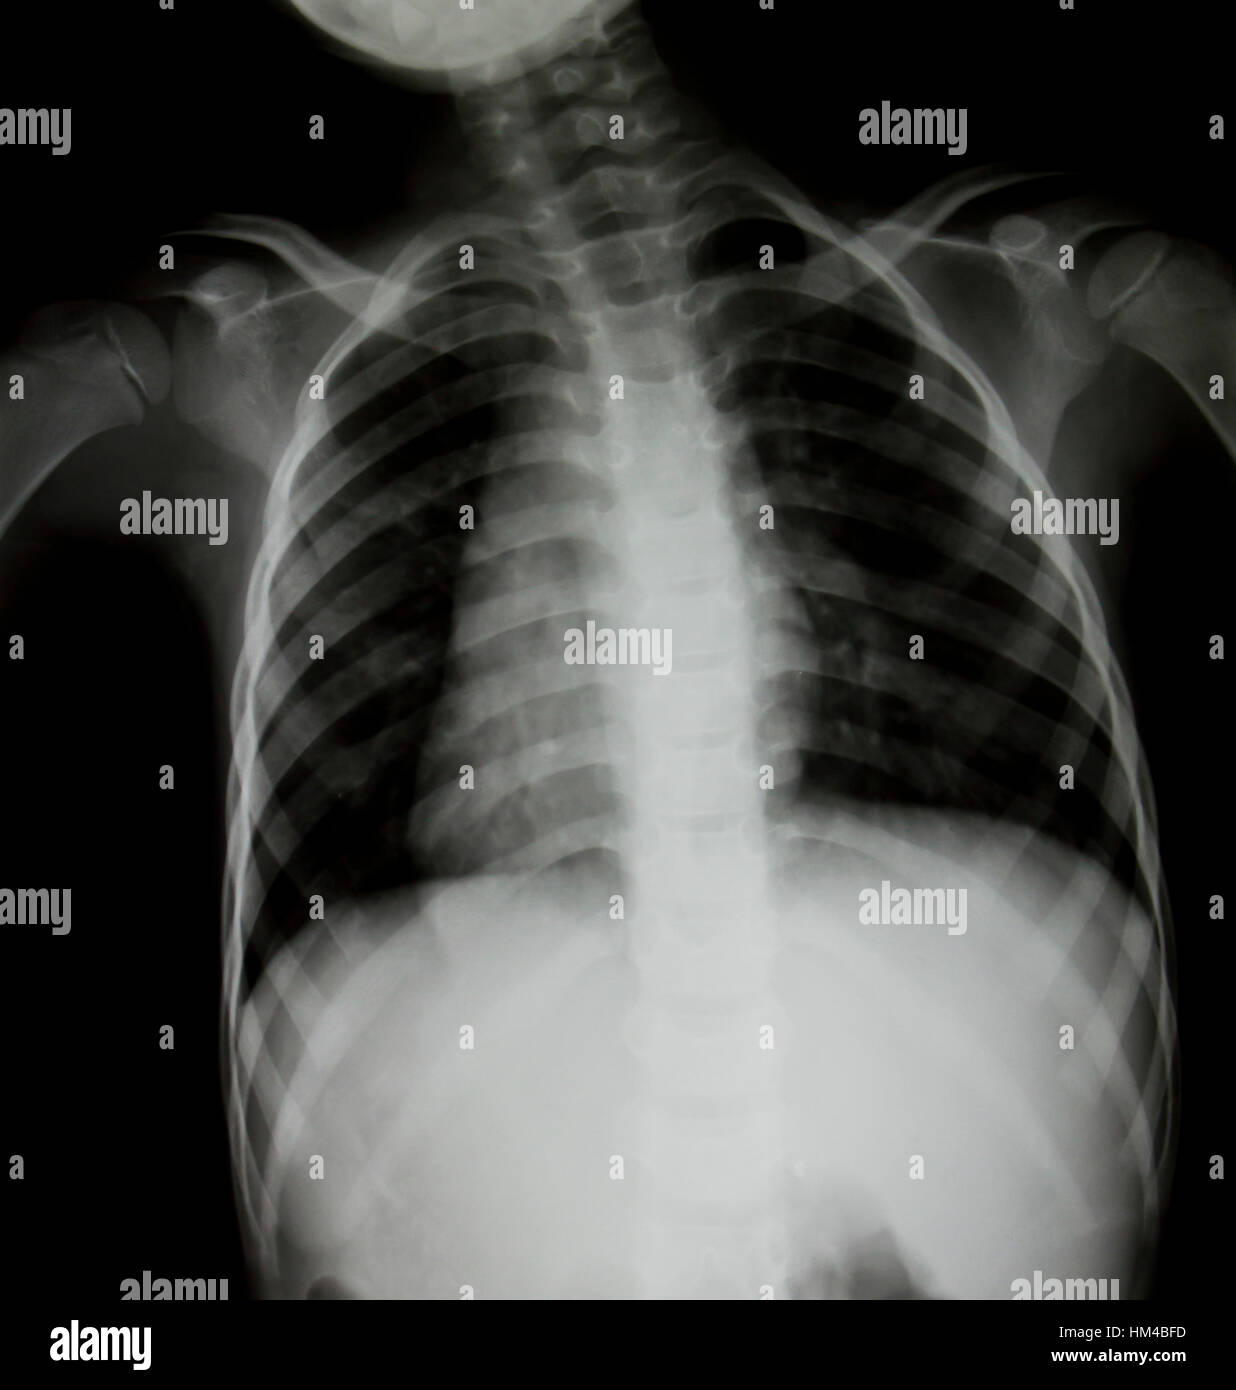

human full chest bone